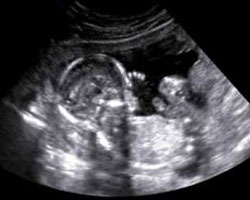

Em seguida vamos mostrar-te um interessantíssimo vídeo com imagens de um feto de 18 semanas em movimento, além de uma ecografia desta mesma semana. Não podes perder!

Ecografia das 18 semanas